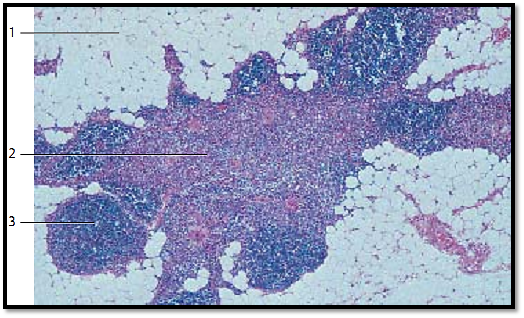

Thymus

The specific thymus tissue organization slowly disappears in puberty (puberty involution). In the adult thymus, lobules are no longer present. Then the fatty involution ensues (age involution ), which initially affects the cortex more than the medulla. Finally, the residual thymus organ consists mainly of degenerated medullary tissue strands. Note the enormous increase in adipose tissue 1.

1 Adipose tissue

2 Medulla with Hassall corpuscle

3 Residual cortex tissue

Stain: alum hematoxylin-eosin; magnification: × 30

Thymus

Physiological changes in the course of human aging lead to almost complete degeneration of the thymus (age involution). In the process, the cortex 1 becomes deplete of lymphocytes. The strands of tissue in the medulla become smaller and reticular connective tissue invades from the outside, to be replace d by adipose tissue 2 . The result of this involution process is a residual thymus with mostly adipose tissue (adipose thymus organ ). At this stage, only scarce remnants of the specific organ tissue are left.

1 Residual thymus, cortex

2 Adipose tissue

3 Hassall corpuscles

Stain: alum hematoxylin-eosin; magnification: × 10